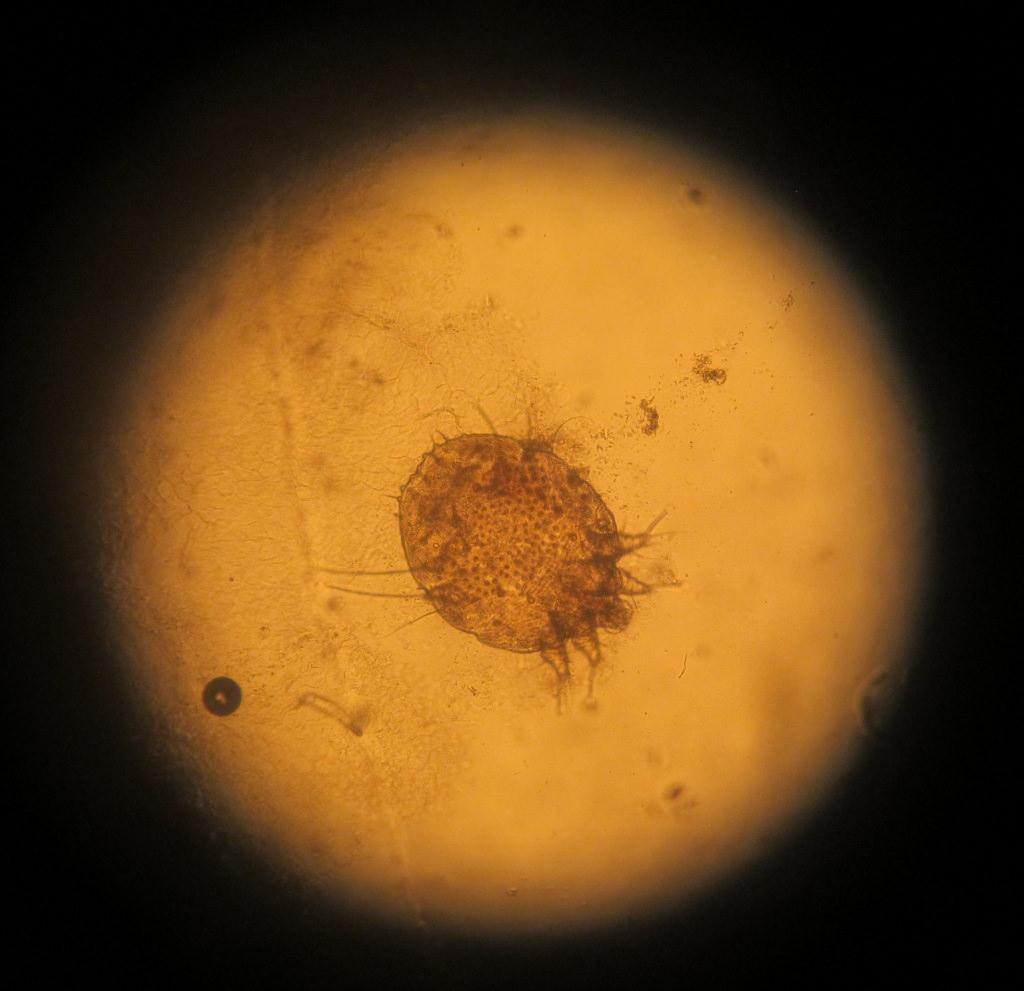

Причина появления поражений – паразит Sarcoptes scabiei. Переносить его может любое живое существо, которое подверглось заражению. И чем больше поражений на теле больного, тем выше риск, что он может кого-то заразить.

как выглядит чесоточный клещ

Заражение осуществляют самки и личинки. Самка обитает в коже. В дневное время она неактивна, но вечером она активно прогрызает ходы, размножается, питается и выделяет продукты переработки. Следовательно, самый большой риск заразиться появляется именно в вечернее-ночное время, когда клещ проявляет большую активность.

Болезнь быстро распространяется по причине того, что самка откладывает яйца, из которых вылупляются личинки. После созревания последние выползают наружу для спаривания. Самец погибает, а самка снова внедряется в кожу человека, чтобы продолжить цикл размножения и распространения.